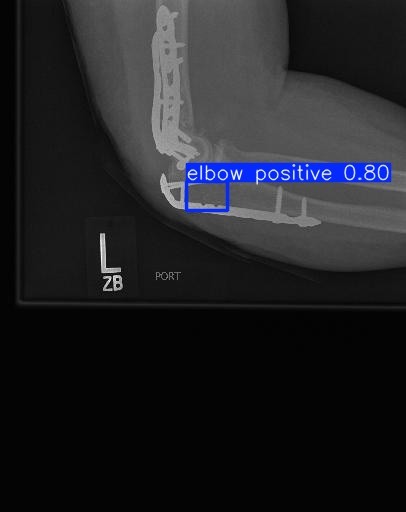

Fracture Detection & Localization

Detect Fractures in Real-Time

Analyze X-rays in real-time to detect fractures and highlight them with Box

Flag potential fracture zones and generate visual overlays to assist radiologists during diagnosis.

We build deep learning models for fracture detection using custom YOLOv8 and Grad-CAM for best result and great accuracy.